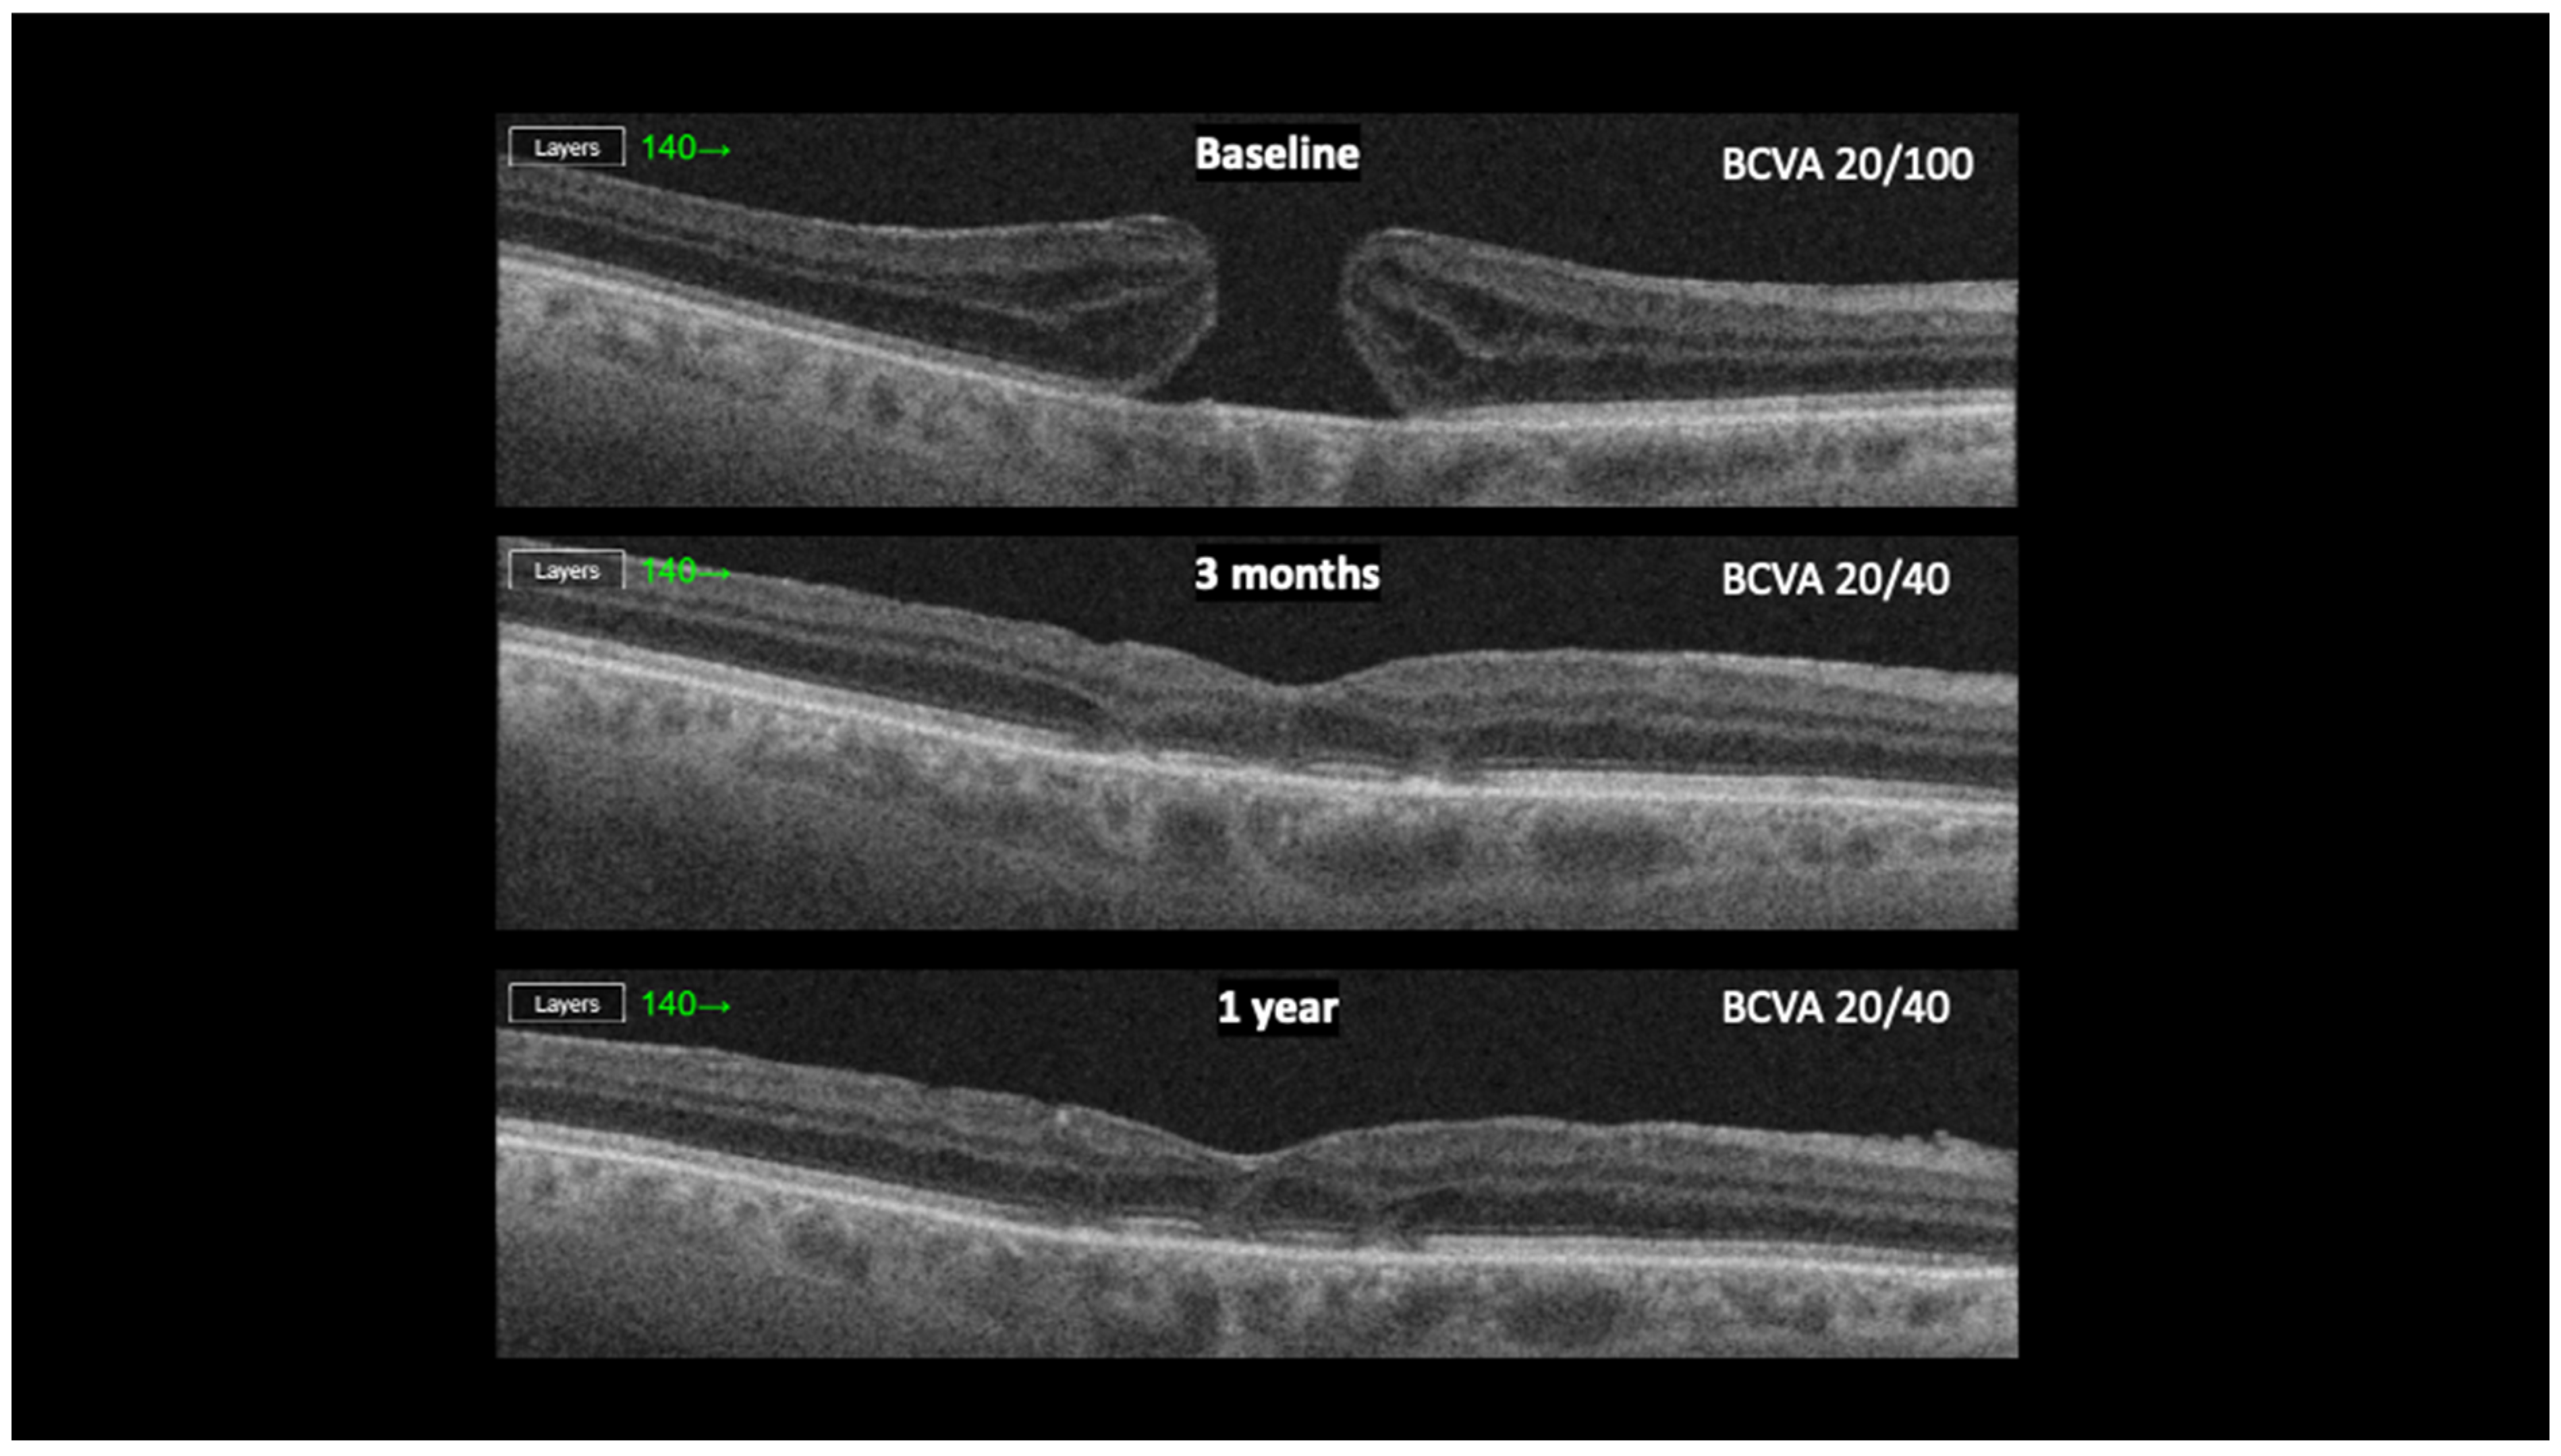

3. Results